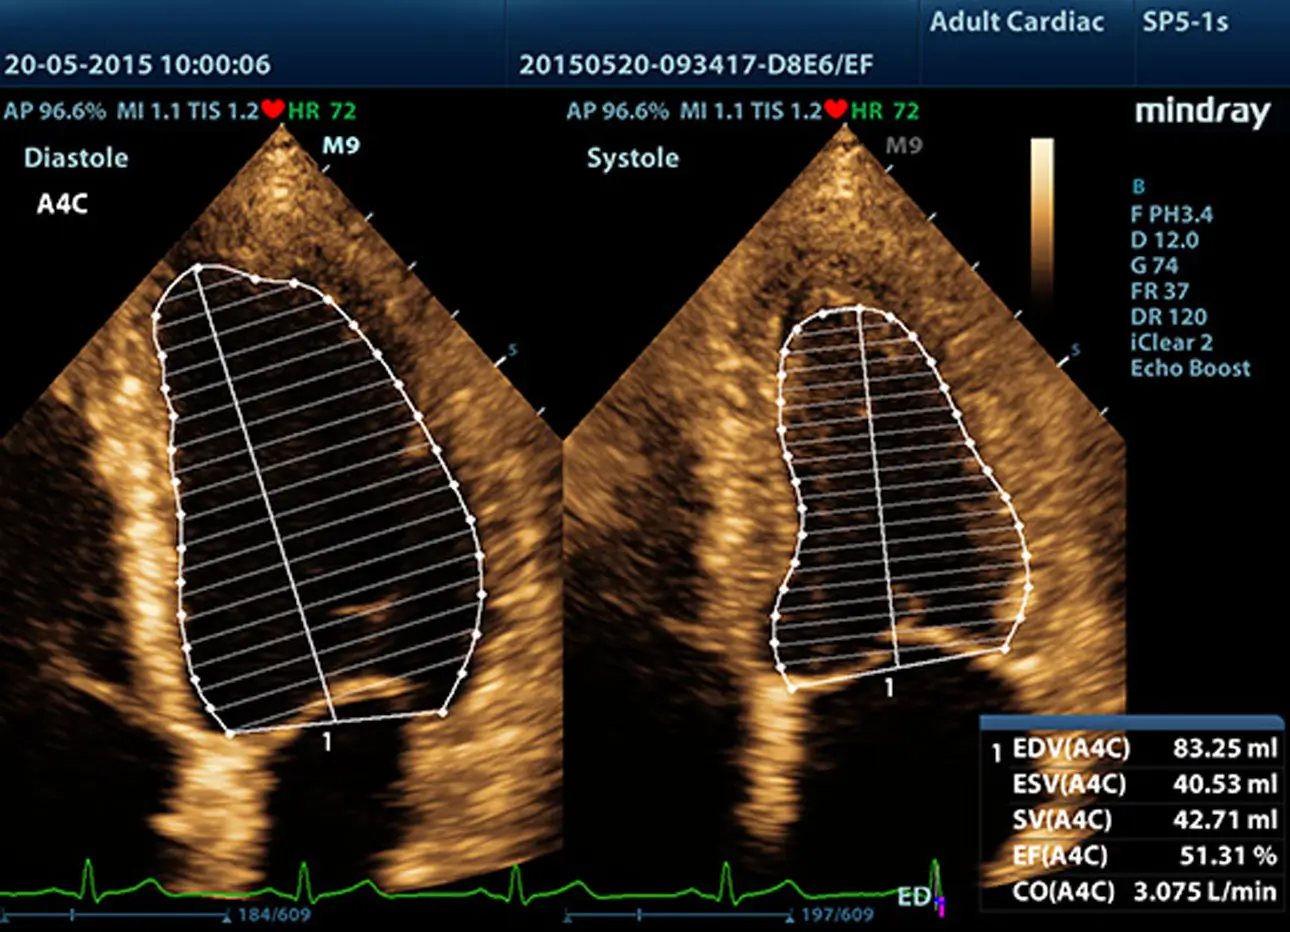

Zaawansowane elementy do przesyłania i odbierania sygnału zapewniają wysoką czułość i dokładność wykrywania echa. Innowacyjne technologie zastosowane w sondach pozwalają na lepszą penetrację i wyższą rozdzielczość, co znacznie poprawia możliwości diagnostyczne.

Sondy wykonane w technologii 3T

Opatentowana technologia wykorzystywana w sondach Firmy Mindray zwiększa zakres obrazowania i wydajność transmisji.

- Dzięki potrójnej warstwie dopasowania uzyskujemy lepszą czułość, szerszy zakres obrazowania i lepszy współczynnik sygnał / szum (S/N)

- Konstrukcja z całkowitym odcięciem wpływa na zmniejszenie zakłóceń, lepszą kierunkowość i poprawę rozdzielczości

- Kontrola termiczna polepsza transmisję akustyczną.